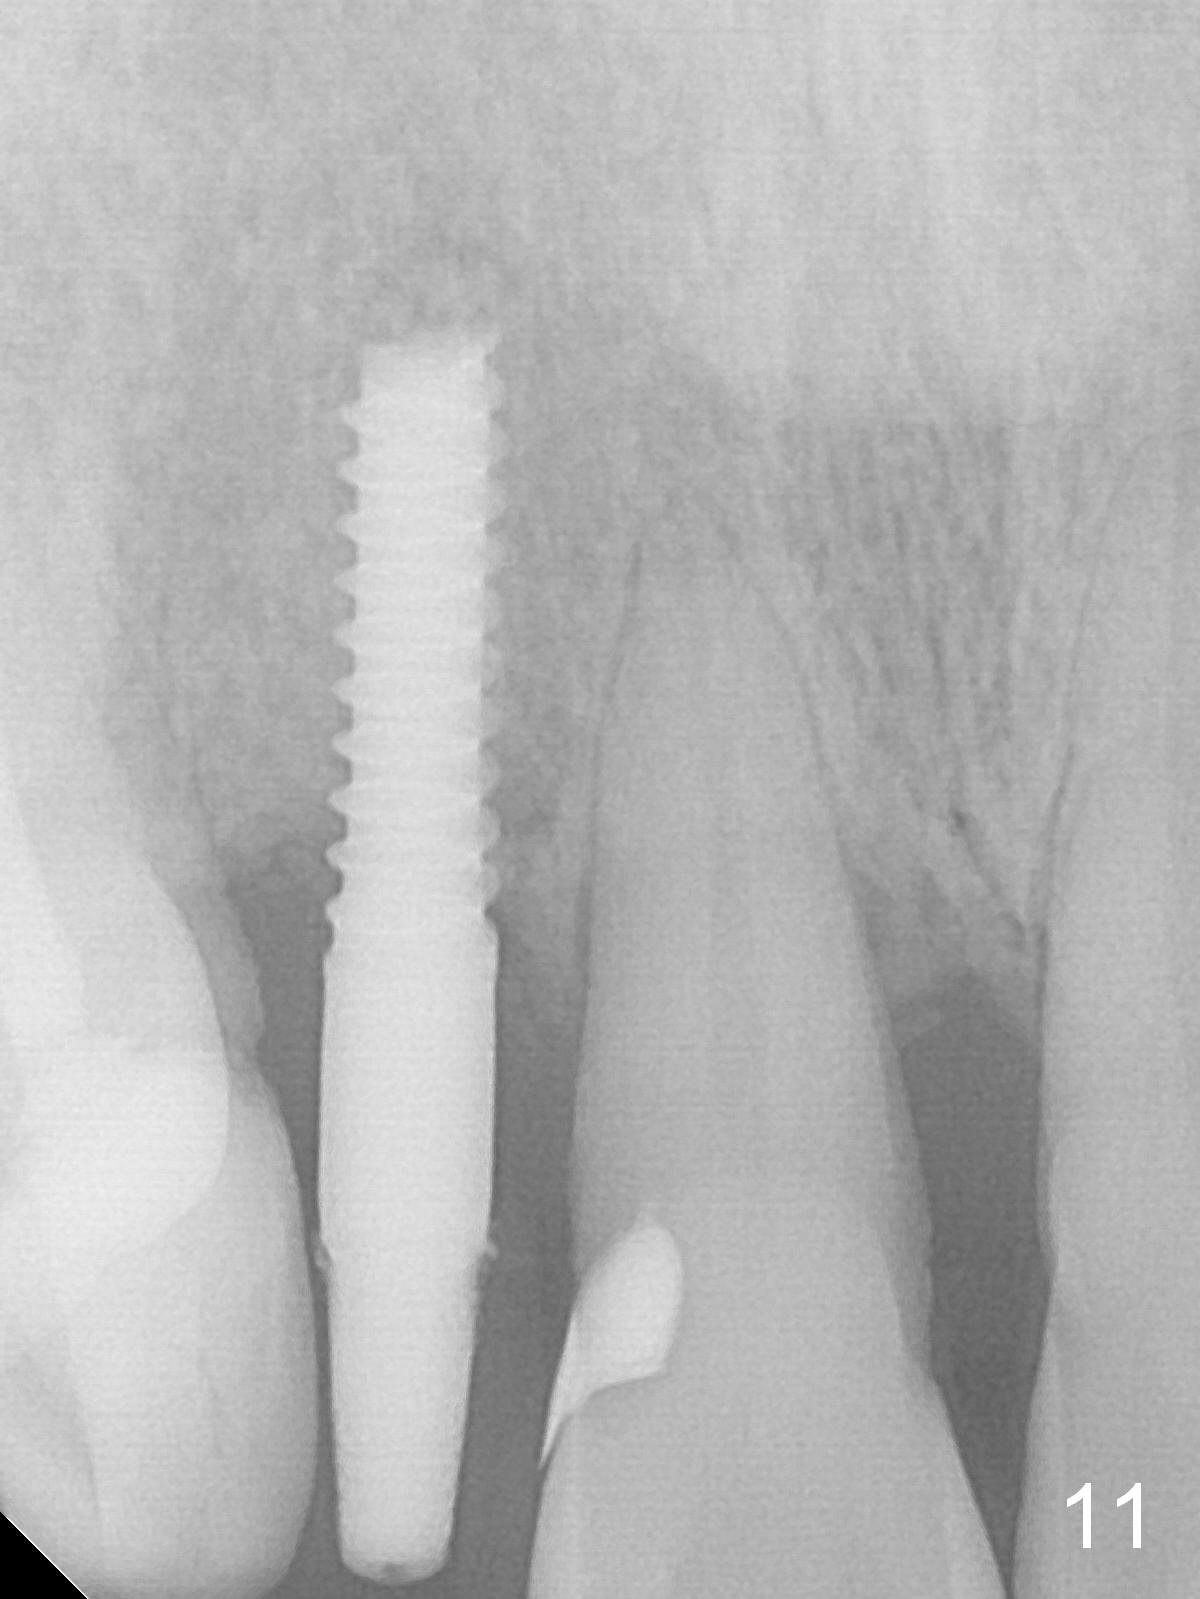

Preop exam shows the apparent wide ridge at #7 (Fig.1). What is ignored preop is the concavity in the apical buccal region (Fig.2 *). When a 3x16(4) mm 1-piece implant is being placed (Fig.3 *, flapless), the apical buccal plate vibration is felt. The biggest mistake is that initial osteotomy is ~ 6 mm shy of the implant length, partially because of 6 mm gingival height. Since the tooth #6 is symptomatic after RCT with paste overfill (Fig.4 >), apicoectomy is contemplated at #6 with exploration of the buccal plate at #7 (Fig.5). Since the implant appears to be long enough, implant apical resection is performed (Fig.6). Since there is coronal thread exposure due to previous periodontitis (Fig.7 <), bone graft is placed in these 3 defective areas after decortication.

Extending the initial osteotomy to the full length of the implant is critical. If perforation is detected early, the trajectory can be changed. Incision should be made if there is no CBCT study. The incision heals 1 and 4 weeks postop (Fig.8,9). The patient returns for final restoration 6 months postop. Apical defects appear to have healed at #6 and 7 (Fig.10,11). Fig.12 is taken 11 months postop and 5 months post cementation. The patient has an accident 9 months post cementation. In fact the implant is alright, while the tooth #6 fractures and #8 subluxates.